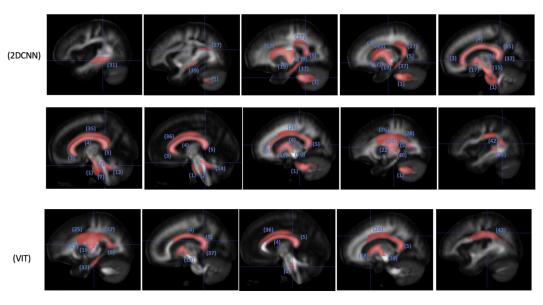

White matter regions in selected MRI slices

White matter regions in selected MRI slices with significant (p < 0.05) impact on classification pro-bability. The AI models correctly identified the sex of subject scans between 92 percent and 98 percent of the time. (from Scientific Report 14, 9835 (2024)).